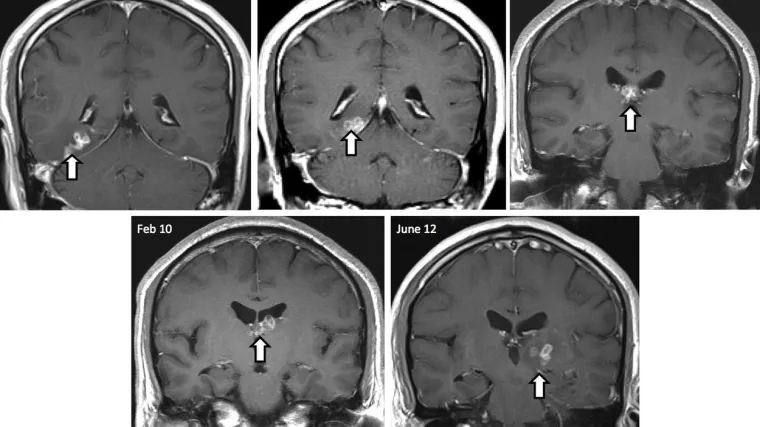

Naime, 2018. godine u njegovu su mozgu otkrili 12 centimetara dugu trakavicu koju su prvo pokušali izvaditi neoperativnim putem jer se nalazila na mjestu vrlo riskantnom za operacije.

No, trakavica je nastavila živjeti u Leijevu mozgu pa je ipak završio na operacijskom stolu. Nakon dvosatne operacije liječnicu su uklonili parazita kojeg inače nalaze u probavnom traktu pasa i mačaka, ali vrlo rijetko se nalazi kod ljudi.

"Trakavica je bila živa i kretala se po mozgu pacijenta. Morali smo ukloniti sve kako ne bi ponovno narasla", rekao je za lokalne medije dr. Gu koji je izveo operaciju te dodao kako je njegova bolnica samo ove godine imala već četiri slična slučaja.